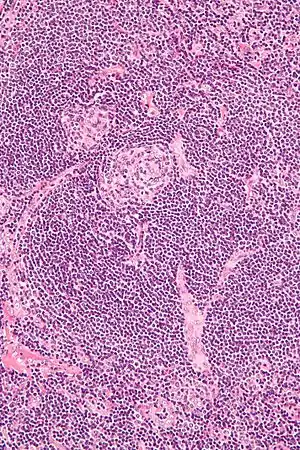

| Micrograph of Castleman disease showing hyaline vascular features including atrophic germinal center, expanded mantle zone, and a radially penetrating sclerotic blood vessel ("lollipop" sign). H&E stain. | |

Castleman disease is defined by a range of characteristic features seen on microscopic analysis (histology) of tissue from enlarged lymph nodes.[10] Histologic features consistent with Castleman disease are categorized into common patterns:

- Hyaline vascular: regressed germinal centers, follicular dendritic cell prominence or dysplasia, hypervascularity in interfollicular regions, sclerotic vessels, prominent mantle zones with an “onion-skin” appearance.[11]

UCD most commonly demonstrates hyaline vascular features, but plasmacytic features or a mix of features may also be seen.[7] iMCD more commonly demonstrates plasmacytic features, but hypervascular features or a mix of features are also seen. All cases of HHV-8-associated MCD are thought to demonstrate plasmablastic features—similar to plasmacytic features, but with plasmablasts present.[10] The clinical utility of subtyping Castleman disease by histologic features is uncertain, as histologic subtypes do not consistently predict disease severity or treatment response.[10]